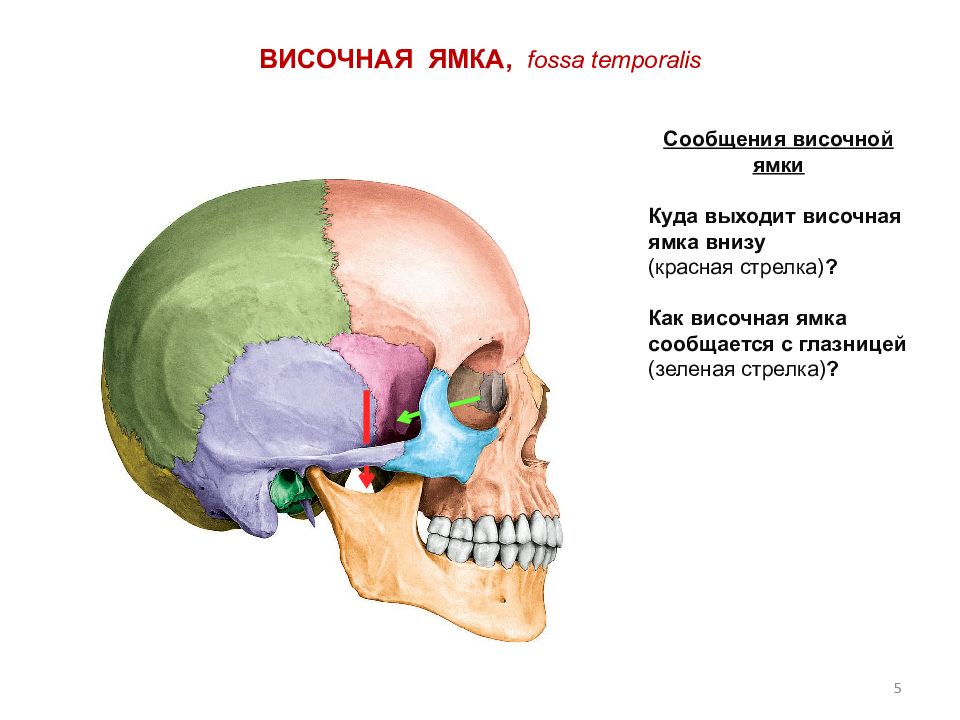

Анатомические особенности: фотографии ямок черепа, височной и подвисочной крылонебной